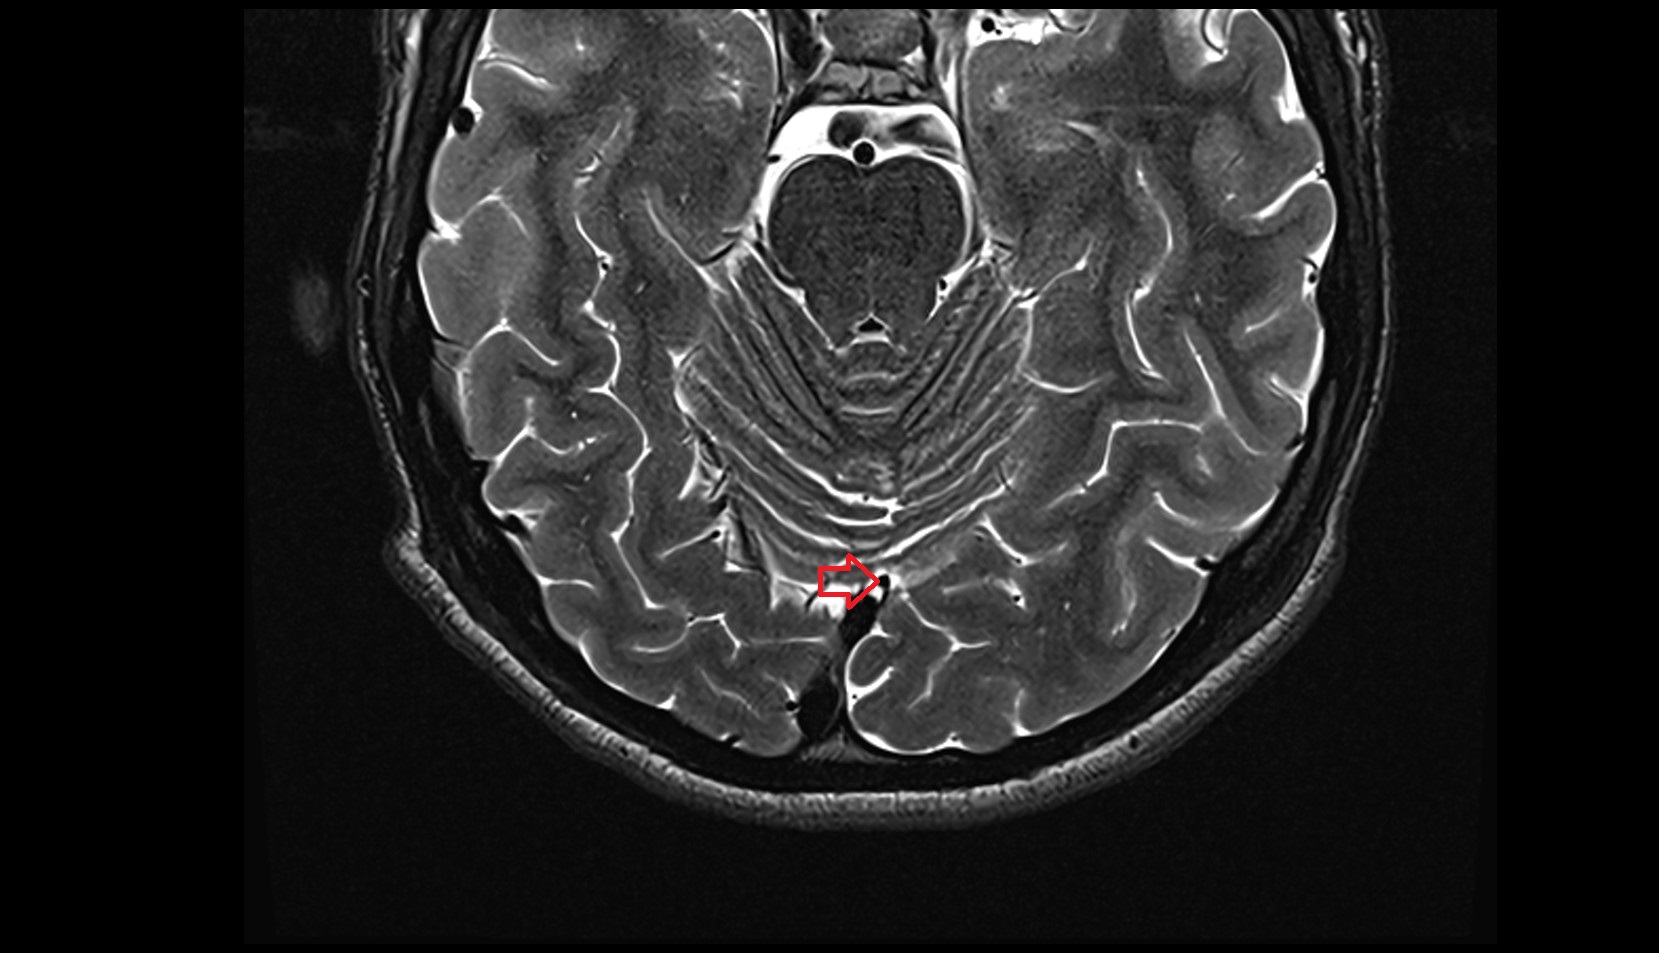

- Median aperture of fourth ventricle (foramen of Magendie)